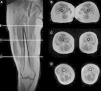

Teniendo en consideración el hecho de obtener mediciones técnicamente reproducibles y la escasa variación debida a condiciones que alteran la intensidad de señal en otras secuencias, la técnica de Dixon parece ser la alternativa para la determinación confiable de la fracción grasa en pacientes con reemplazo graso muscular23,24. Sin embargo, la evaluación por imágenes de los pacientes portadores de miopatías congénitas muestra cómo, en muchas ocasiones, el reemplazo no es homogéneo dentro del plano de sección del músculo, reconociendo áreas de músculo respetado que se alteran con tractos de grasa de diferente tamaño y que pueden configurar regiones con mayor reemplazo graso, especialmente dentro de los músculos largos (fig. 1).

Variabilidad en el tamaño y posición del ROI: el reemplazo graso no suele darse como un aumento difuso de la señal del músculo afectado. Muy por el contrario, el cambio en resonancia suele verse tanto como áreas de músculo con señal relativamente normal que se alternan con tractos adiposos de alta señal, como áreas grises, más uniformes de límites variados, cambios que con frecuencia son progresivos (fig. 4). La elección de un ROI de pequeño tamaño, en forma aislada, puede determinar la elevación o normalización de la señal en un rango que puede llegar hasta el 80%, dependiendo la posición respecto de la presencia de áreas relativamente más preservadas o áreas de franca infiltración (fig. 5). La selección de múltiples mediciones en una misma área o de un área que se acerque a los límites del músculo permite dar cuenta, en una medida promedio, de la coexistencia de tractos fibrosos de diferente calibre y de fibras musculares preservadas. Al evaluar la diferencia entre realizar varias mediciones pequeñas y una medida que abarque el total del músculo, no existieron diferencias significativas entre el promedio aritmético de los valores de los 5 ROI pequeños y el valor de un ROI del área de sección para 107 músculos por paciente (p=0,0749).